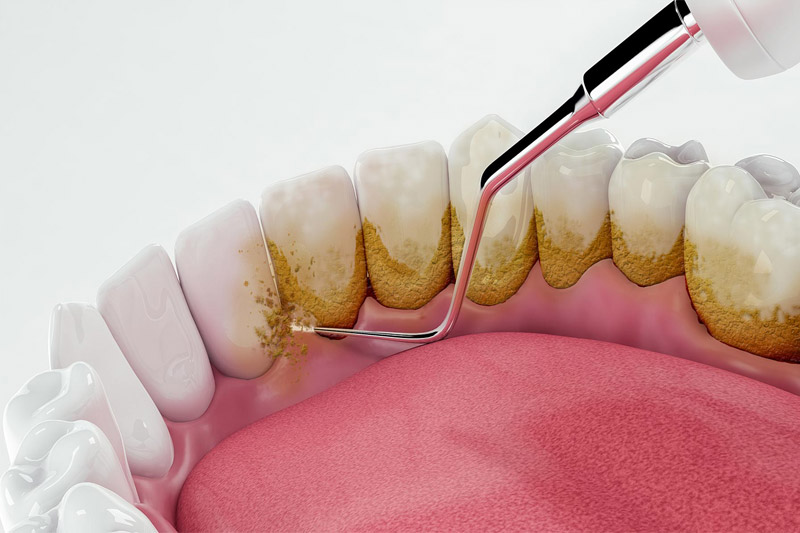

جرمگیری

زمانی که عفونت لثه در مرحله اولیه ژنژیویت (Gingivitis) است میتوان از جرمگیری دندان برای درمان آن کمک گرفت، در فرایند جرمگیری به علت از بین رفتن کامل تمامی جرمها و پلاکهای تشکیل شده روی دندان از تحریک و افزایش میزان چرک در لثه جلوگیری میشود و اگر این بیماری درمراحل اولیه باشد انجام جرمگیری مانع ایجاد پریودنتیت خواهد شد.